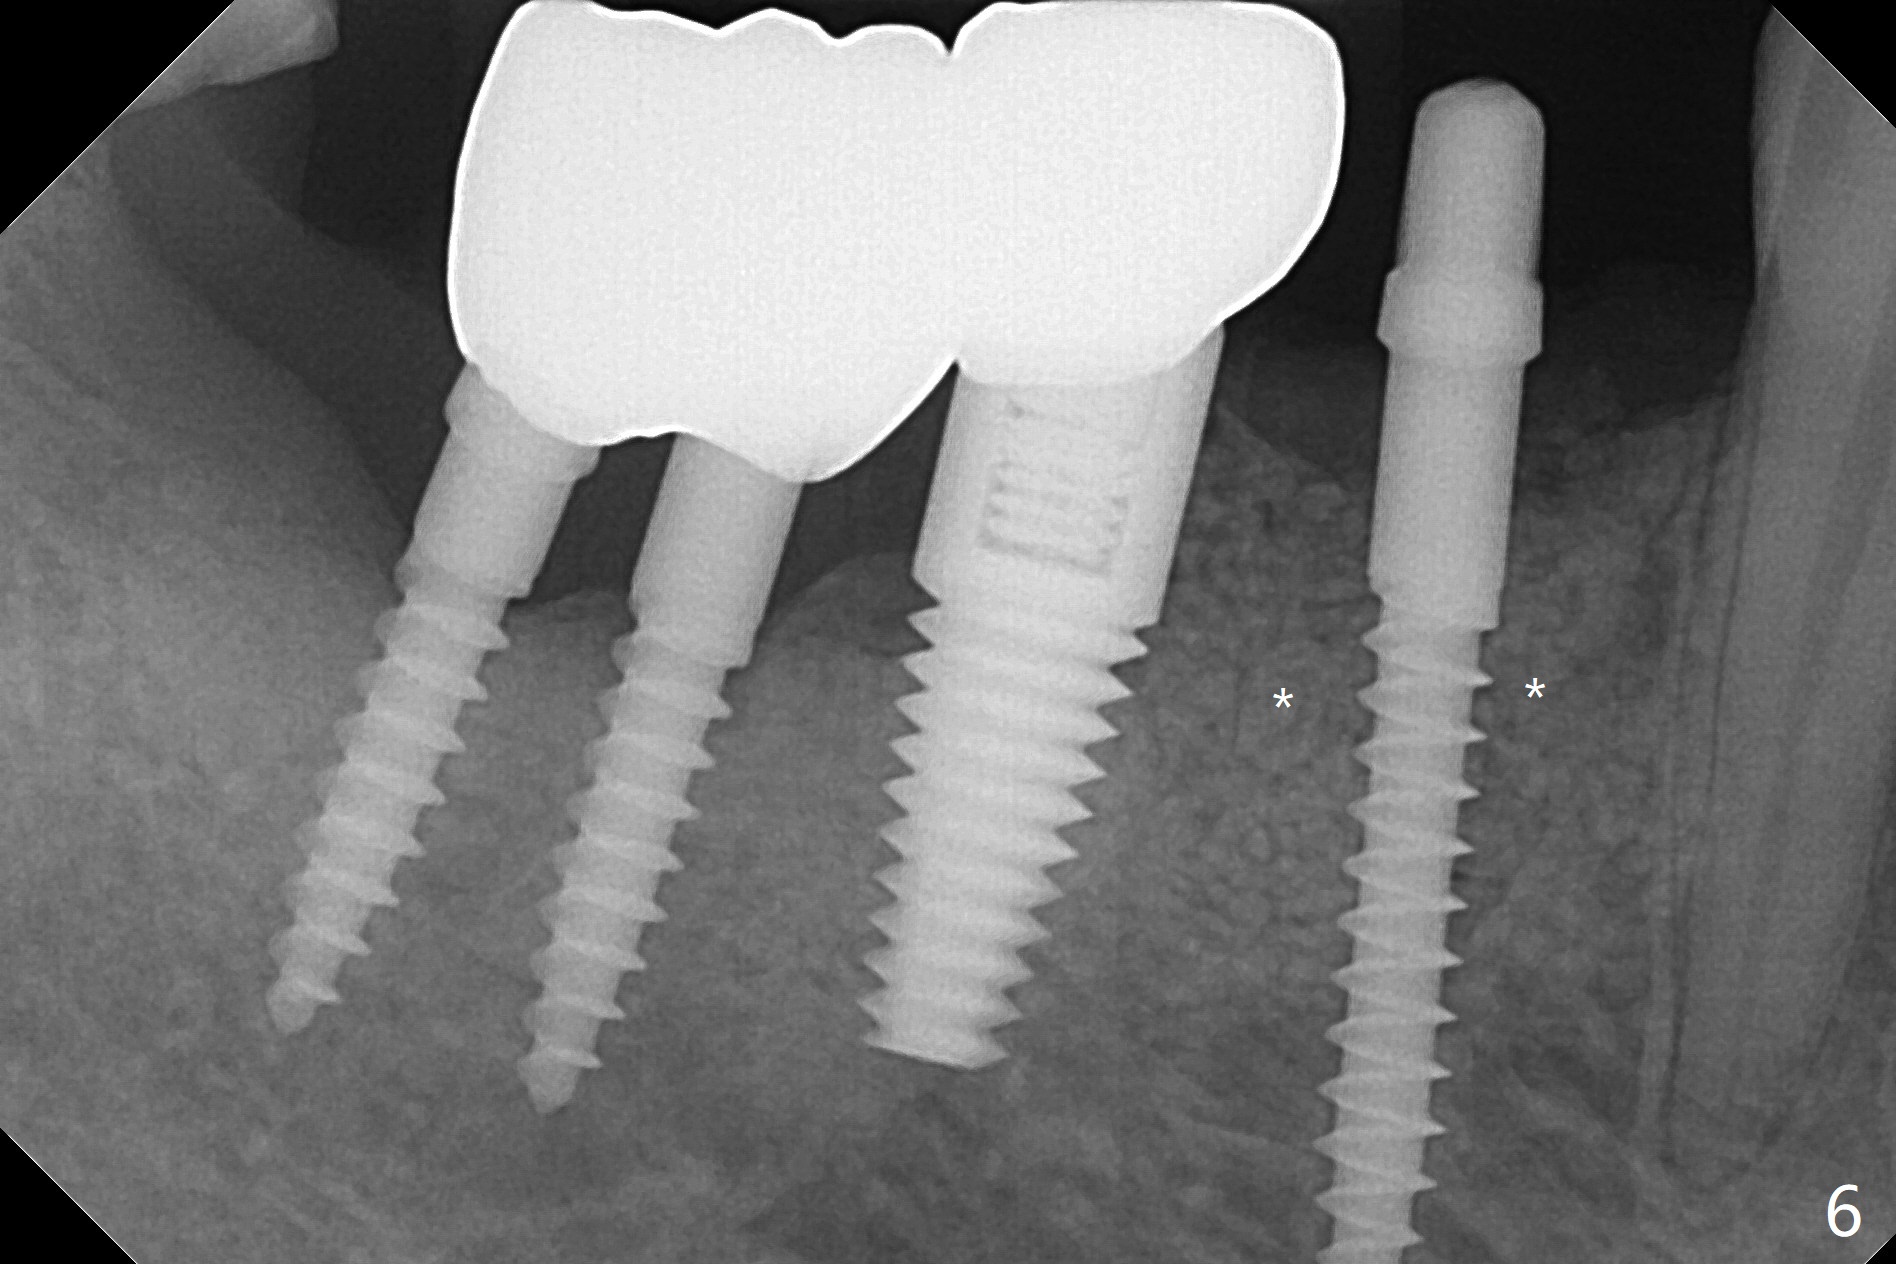

61岁女右下4(粘固后5.5年)植体周围炎(颊侧牙龈没有角化龈(图一:*)),因为颊侧种植(图二),翻瓣证实(图三),取出4.5毫米两段式植体,在舌侧骨质(图四:L)即刻植入2.5毫米一段式植体(图五),颊侧缺损植入大量粘性骨粉(图六:*),覆盖PRF膜后,缝合(图七),与图二对比,窄植体明显舌侧移位。术后一个月撤除牙周敷料(图八),并没有马上制作临时牙冠,让病人容易搞好局部卫生,促进伤口愈合(图九),术后三个月塞入龈线(图十:^),制备基台,植体在牙槽嵴中性位置(颊舌侧),但愿颊侧有足够再生骨质,覆盖植体螺纹。